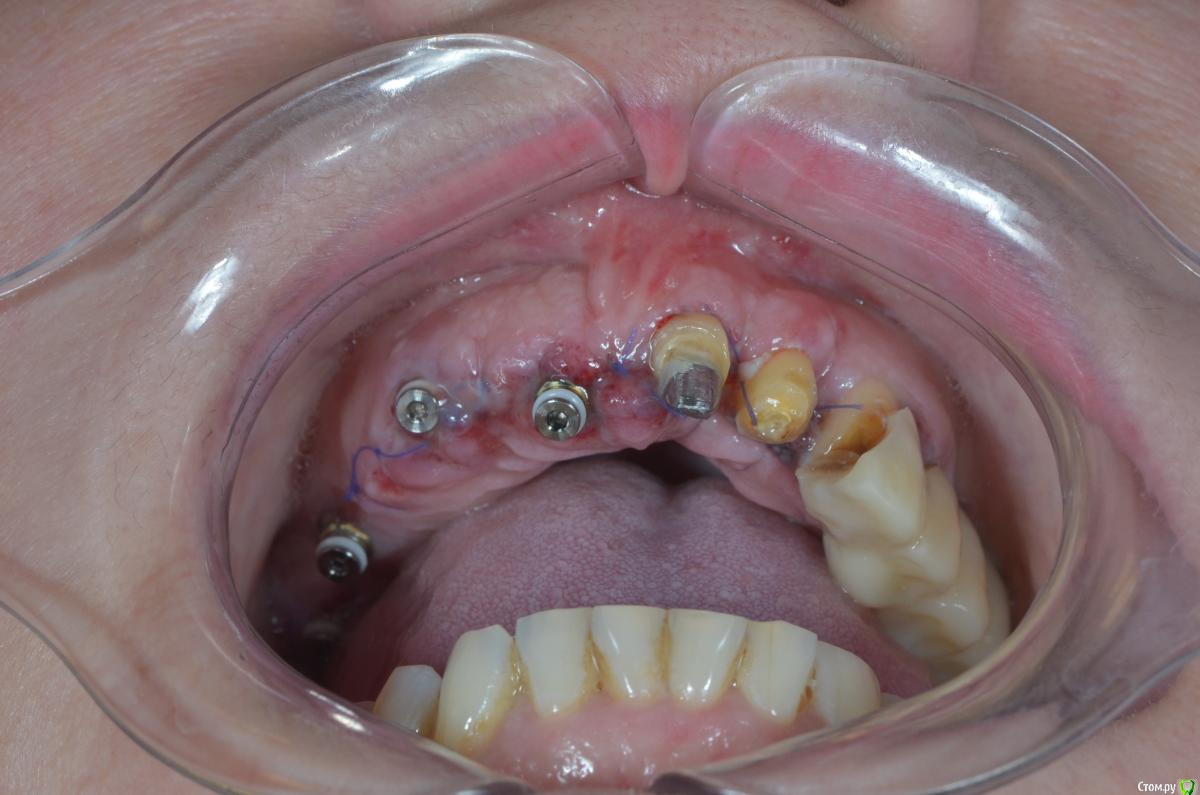

gangsta85 Опубликовано 22 декабря, 2018 Поделиться Опубликовано 22 декабря, 2018 Коллеги подскажите с тактикой протезирования?Есть проблема , хирург сильно укоротил зениты 21,22,23 .Работа с немедленной нагрузкой, торк 50н.Думаю сделать 2 фрезерованных моста с розовой десной, на зубы и имплантаты.благодарю) Ссылка на комментарий

gangsta85 Опубликовано 23 декабря, 2018 Автор Поделиться Опубликовано 23 декабря, 2018 13 переустановить пока не поздно.Думаю установить на 13 мультиюнит. Ссылка на комментарий